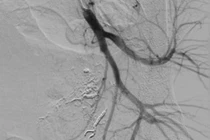

| Hình ảnh dị vật kẹt trong tim bệnh nhân (Ảnh - BVCC) |

Đến tháng 11/2021, sau 6 năm, dây nối của buồng truyền bị đứt, trôi theo mạch máu và bị kẹt lại trong tim của bà H. Tại Bệnh viện Hữu nghị Việt Đức, các bác sĩ đã can thiệp lấy dị vật cho bệnh nhân.

ThS.BS. Thân Văn Sỹ - Khoa Chẩn đoán Hình ảnh, Bệnh viện Hữu nghị Việt Đức - cho biết: Các bác sĩ đã sử dụng dụng cụ can thiệp đưa vào buồng tim và lấy dị vật ra ngoài cho bệnh nhân chỉ trong vài phút. Quá trình can thiệp nhanh chóng và nhẹ nhàng đến nỗi người bệnh phải thốt lên trong ngỡ ngàng, khi ôm nỗi sợ phẫu thuật suốt 6 năm, không dám vào viện để lấy buồng truyền ra cho tới khi xảy ra biến chứng nguy hiểm. Sau can thiệp, bệnh nhân ổn định, dự kiến sẽ được xuất viện trong 1-2 ngày.